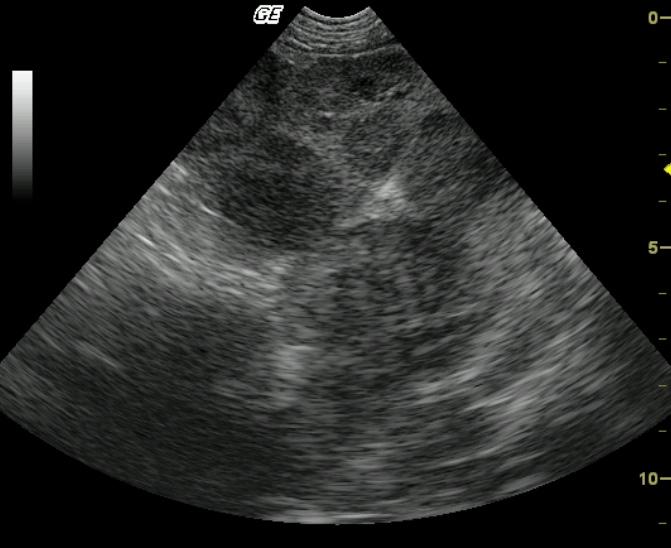

A 10 year old MN Pug was presented for the evaluation of anorexia, vomiting, diarrhea, and pollakuria. No abnormalities were noted on the physical exam. The CBC showed a neutrophilia, monocytosis, and thrombocytopenia. A serum biochemical profile revealed elevated serum alkaline phosphatase, elevated ALT, elevated AST, elevated GGT enzyme activities as well as hypercholesterolemia.